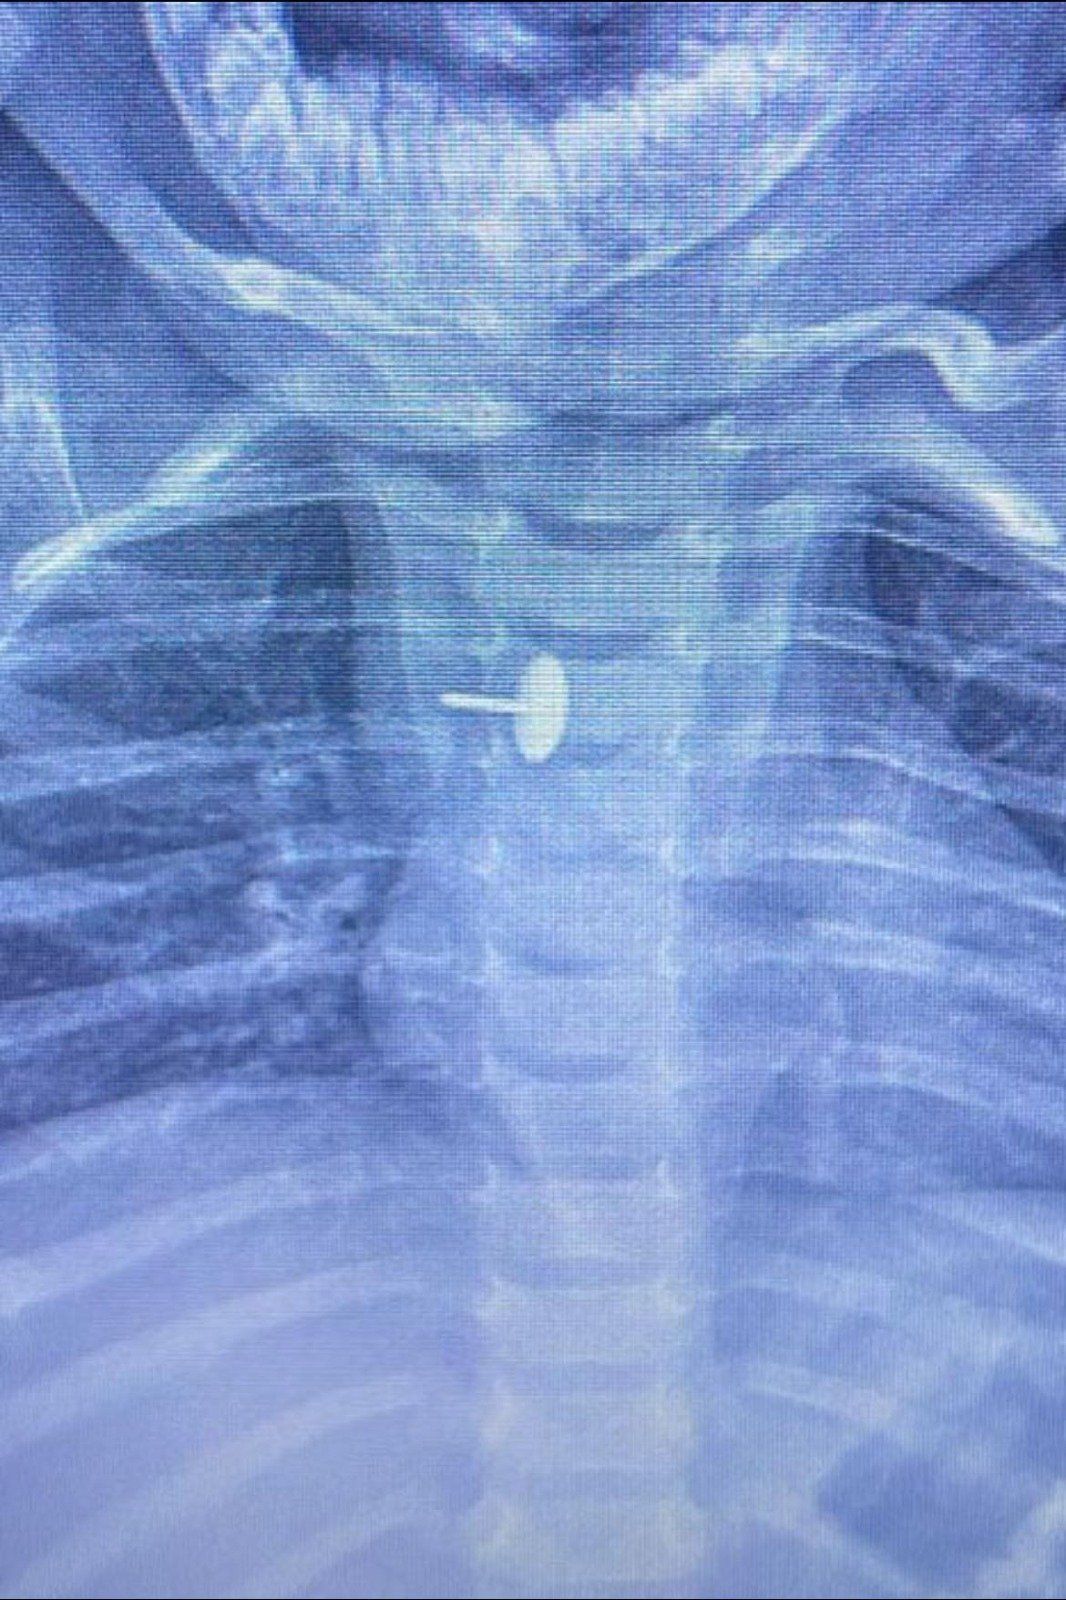

نجح فريق قسم جراحة الأطفال، بمستشفى الأطفال التخصصي ببنها، بمحافظة القليوبية، بقيادة الدكتور محمد متولي رئيس قسم جراحة الأطفال، في إجراء عملية دقيقة لاستخراج دبوس ضغط من مريء طفلة عمرها سنة و7 أشهر، كانت قد ابتلعته منذ 6 أشهر.

الجسم الغريب استقر داخل جدار المرئ

كشفت مستشفى الأطفال التخصصي ببنها، في بيان لها، أن الجسم الغريب استقر داخل جدار المريء، مما تسبب في عدم قدرة الطفلة على البلع طوال هذه الفترة، وجعل حياتها في خطر دائم. استخدام أحدث الأجهزة في الجراحة

أوضحت المستشفى أن العملية تمت باستخدام منظار الجهاز الهضمي، وجهاز الأشعة "سي- آرم"، ومنظار القصبة الهوائية، وسط أعلى درجات التركيز والدقة، ليكتب الأطباء نهاية سعيدة لقصة مليئة بالتوتر والخطر، وضم الفريق الجراحي كلا من الدكتور وليد محمد، والدكتور عبد الله أحمد أخصائي جراحة الأطفال، والدكتور السيد الوصال نائب جراحة الأطفال. تحذيرات وتوصيات من المستشفى للأهل للحفاظ على الأطفال

دبوس ضغط فى مرئ طفلة